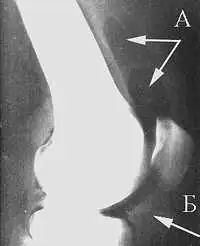

Исход артроза — полное разрушение сустава с формированием анкилоза — полной неподвижности сустава или неоартроза с неестественной подвижностью. Это сопровождается тяжёлым нарушением функции конечности. В последнее время, не дожидаясь исхода заболевания, всё чаще применяют специальные операции по замене сустава протезом — эндопротезирование сустава. На рисунке изображена типичная для терминальной стадии артроза коленного сустава варусная деформация колена в сочетании с боковой патологической нестабильностью коленного сустава. Артроз блоковидного или шаровидного сустава, такого как тазобедренный, завершается анкилозированием. При этом замыкание сустава обычно происходит в нефизиологическом (порочном) положении конечности. В данном случае мы видим бедро в положении сгибания и приведения, при котором нога укорачивается, а ось конечности и биомеханика опорно-двигательной системы существенно нарушается.